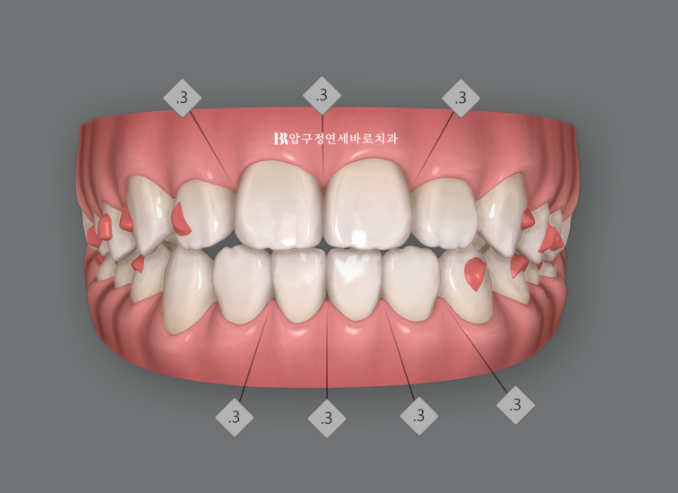

인비절라인 시뮬레이션

클린체크 시뮬레이션상 최종 교합입니다.

계획대로라면 이 시뮬레이션처럼 앞니 중심선이 맞아지고 반대교합이 고쳐져야 하는데 말이죠.

왜 이런 차이가 생기는 지 궁금하시죠?

환자분이 장치를 열심히 안 꼈을 수도 있고, 열심히 꼈더라도 치아나 잇몸뼈는 컴퓨터가 아닌 살아있는 조직이여서 치아가 시뮬레이션 대로 100% 이동하지 않을 수 있습니다.

이런 변수를 대비해서 인비절라인 라이트에서는 1회의 추가제작 기회가 있습니다.